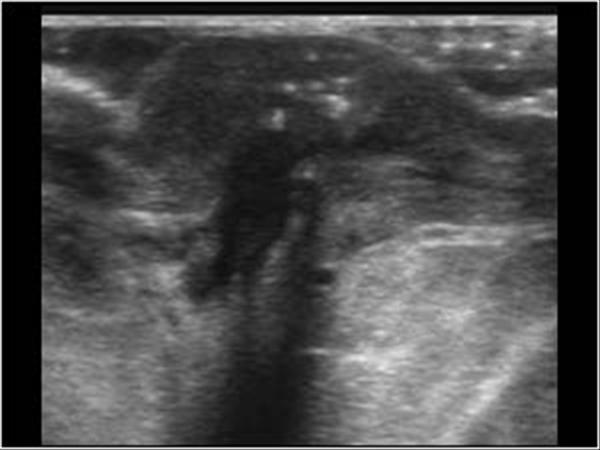

Explain the sonographic appearance of cysts.

anechoic and circular

thin walls

through transmission

What is the Sonographic Appearance of simple cysts?

Oval or round

anechoic

smooth walls

well circumscribed shape

posterior enhancement

edge refraction

sharp anterior and posterior borders

reverberation